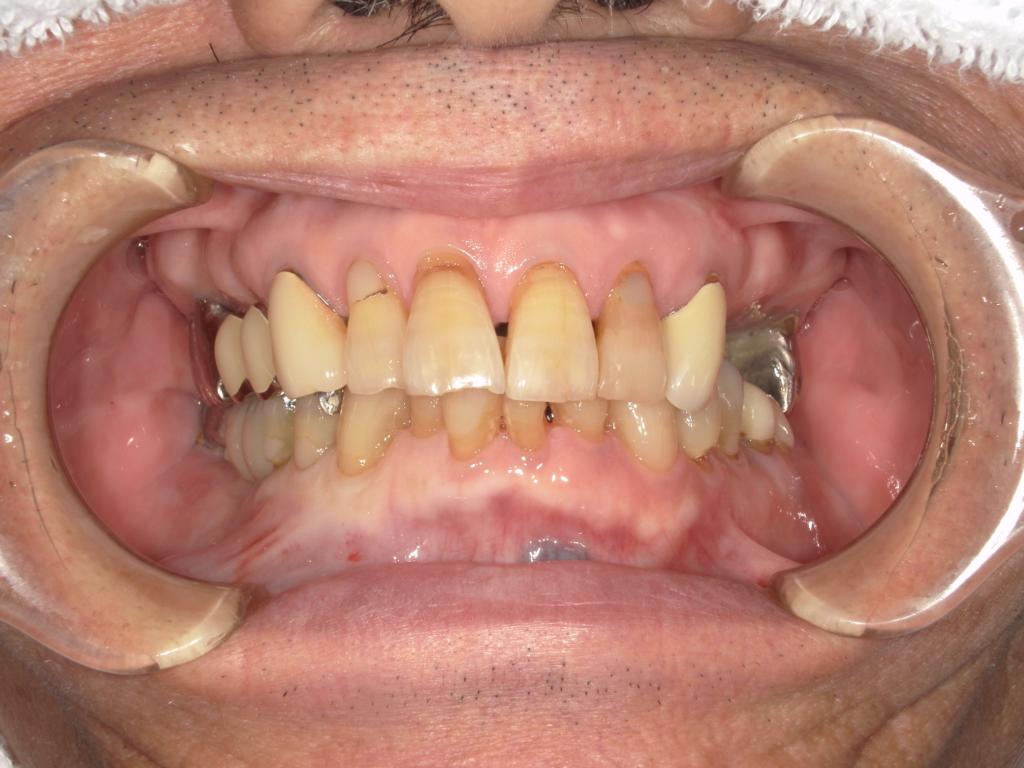

Y様インプラント実例 #44

左の上下の奥歯をインプラントで治療しています。

左下の奥歯は歯を抜くのと同時にインプラントの埋め込みを行っています。

被せものは上下、セラミックスで作っています。

治療前

治療後